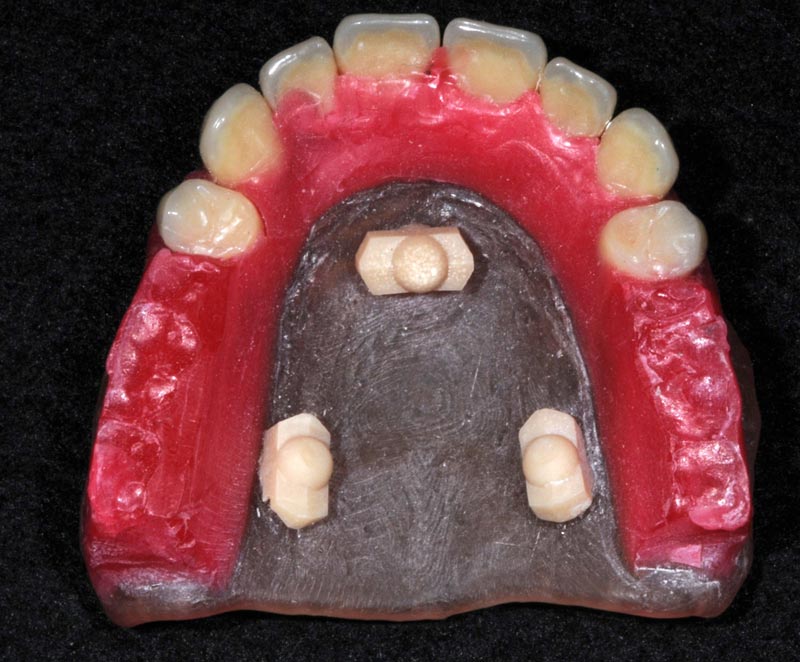

Prova estetica montaggio

Prova estetica con reperi radiopachi